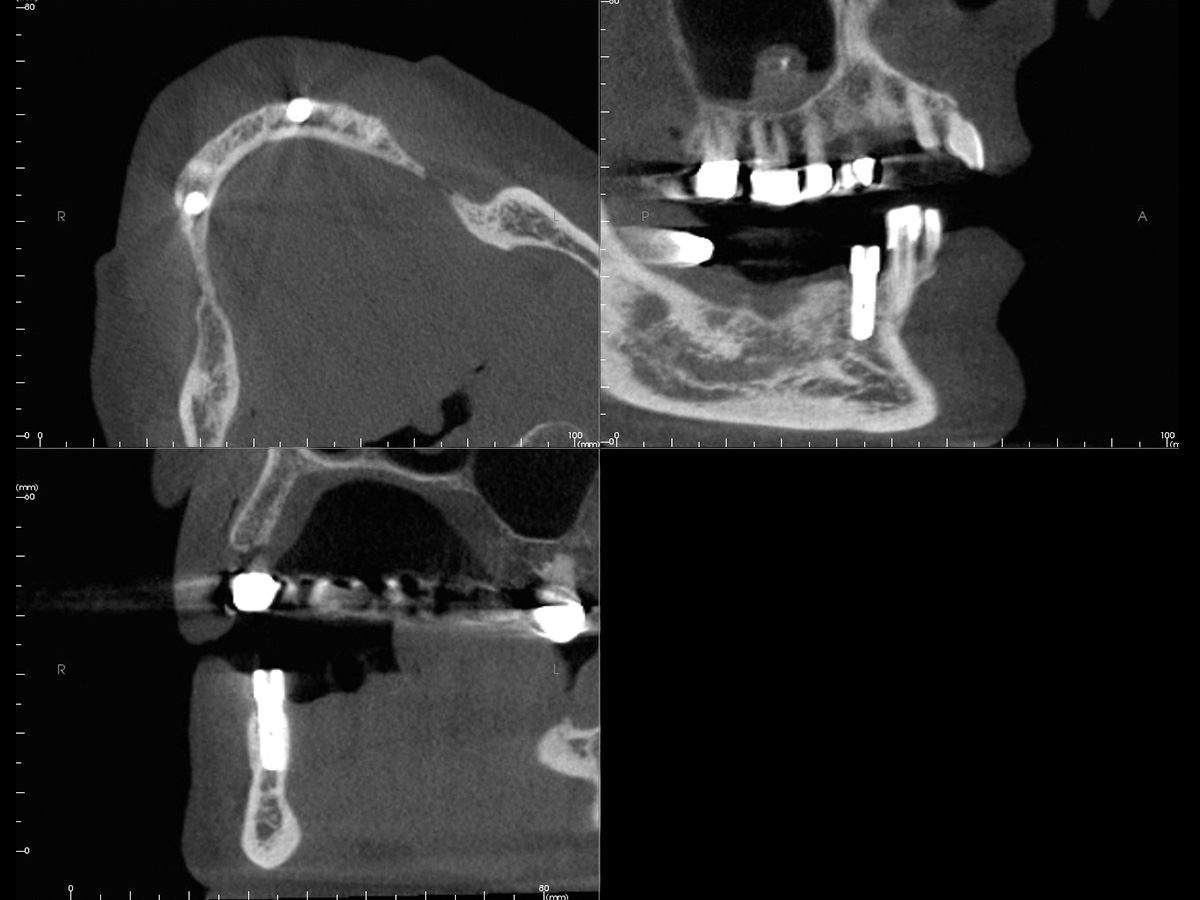

Abbildung 2

DVT mit Implantatplanung zeigt die atrophe Knochensituation mit geplantem Implantat.